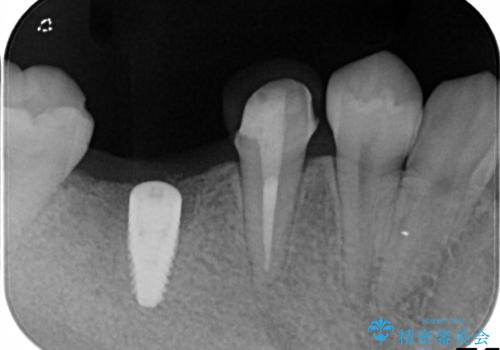

- 右下の奥歯の調子がよくないとのことで来院されました。

レントゲン・口腔内診査をお行い、保存が難しいことがわかりました。

抜歯後インプラントをする計画としました。

見た目では問題がなさそうでも、レントゲン撮影・診査を行うと状態が悪くなっていることがあります。